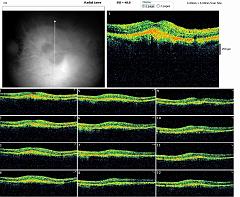

RADIAL LINE OD

RADIAL LINE OG

CROSS LINE OG

COMPARATIF OG